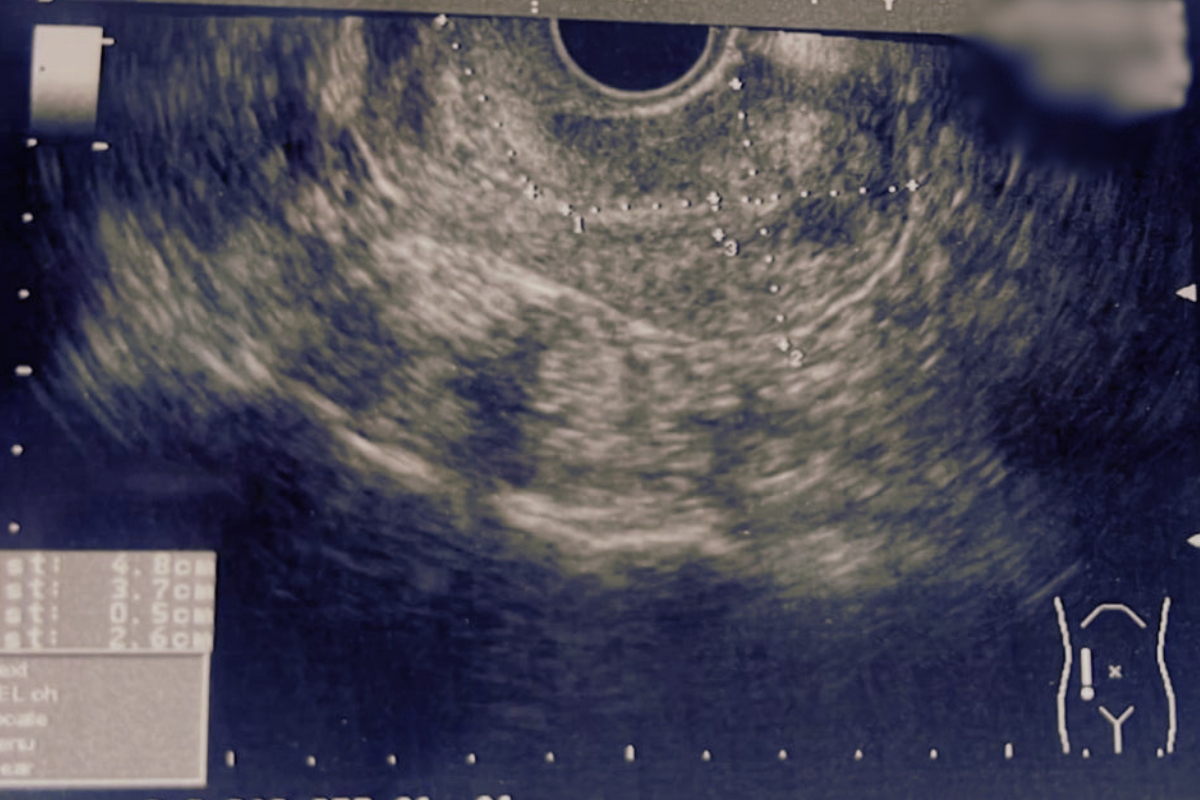

Узел 42 мм

После лечения:

Пациентка готовится к беременности

Узел 1 мм

за 2 месяца

Узел 28 мм

за 4 месяца

"В начале 2024 года начались задержки менструального цикла, до 2-х недель, обильные и болезненные выделения. На УЗИ размер нескольких миоматозных узлов был уже 48х37 мм, 28х35 мм, 43х36 мм. Так как наблюдался рост новообразований, были показания к операции, в другой клинике меня направили на операцию. Я не хотела делать операцию и принимать гормональную терапию, поэтому обратилась в Центр лечения миомы без операции при клинике «Нео Вита» по рекомендации. На сегодняшний день нормализовался цикл, ушла боль, улучшилось настроение и общее состояние. Значительно изменились процессы в личной жизни — это тоже хочу отметить. Размеры узлов 23х14, 12х15 мм. Это большой прогресс, ведь я понимаю, когда убрать у болезни причину – она не вернется и терапия медикаментозная на нужных этапах лечения действительно быстро помогает. Большое спасибо клинике и всем специалистам!"